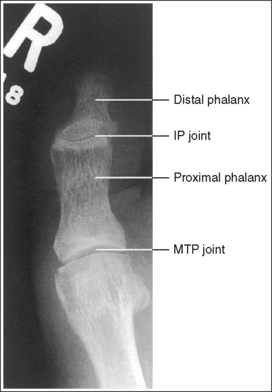

See Figures 6-8 and 6-9 and Box 6-4.

FIGURE 6-8 First lateral toe projection with accurate positioning. DIP, Distal interphalangeal; MTP, metatarsophalangeal.

FIGURE 6-9 Second lateral toe projection with accurate positioning. DIP, Distal interphalangeal; MTP, metatarsophalangeal; PIP, proximal interphalangeal.

The digit is demonstrated in a lateral projection. The posterior surface of the proximal phalanx demonstrates more concavity than the anterior surface, and the condyles are superimposed. The soft tissue outline of the nail, when shown, is in profile anteriorly.